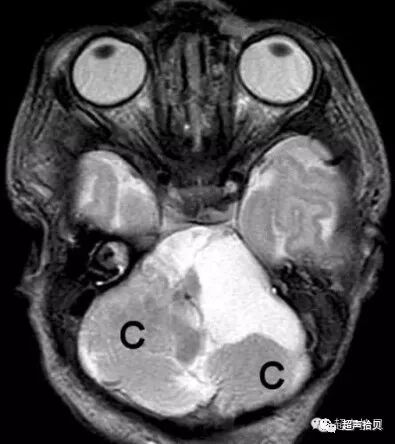

图2:冠状超声图显示位于后颅窝蛛网膜囊肿

足月,大1天新生儿,有蛛网膜囊肿和复杂性后颅窝移位。(a)。超声下左矢状缝旁切面显示小脑前桥小脑角部位脑积水(箭头)(b)超声下经乳突部横断扫查,脑积水范围变大(箭头)。白箭标识为双侧颈内动脉(c)MRT2W横断扫描证实了超声结果,同时在左侧显示偏小的,发育不全的小脑(C)(d)。MRT1W左矢状缝旁切面显示病变与(a)相似